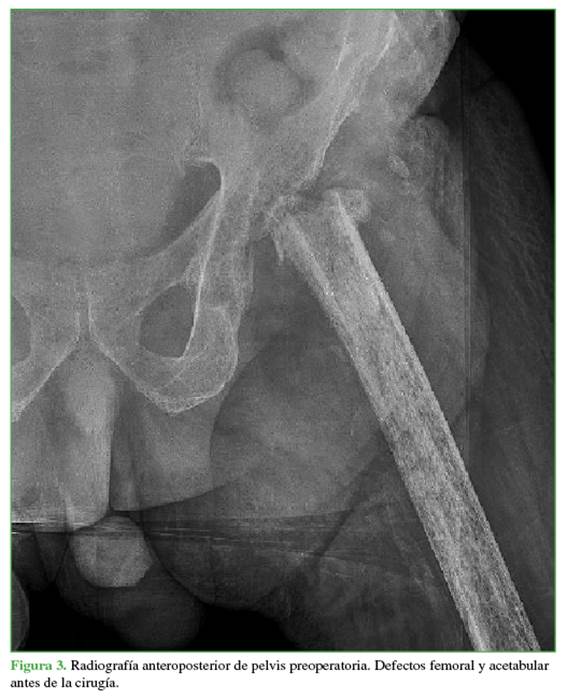

A los tres meses (febrero 2019), tuvo una nueva infección crónica y se decidió realizar otro primer tiempo, en el que se colocó un espaciador de cemento con antibiótico (gentamicina y vancomicina). Durante la cirugía, se detectó un defecto considerable del stock óseo: tenía un defecto femoral tipo IV y un defecto acetabular tipo IIIA de Paprosky.

En junio de 2019, acudió a consultas externas en nuestro centro hospitalario para evaluar el tratamiento definitivo (Figura 3).

En 1994, Paprosky6 definió su clasificación sobre los defectos acetabulares en función de los criterios radiográficos estudiados en una radiografía anteroposterior de pelvis. Los defectos tipo III ya incluyen una pérdida ósea grave de las columnas anterior y posterior, así como de la cúpula superior. Definió el defecto IIIA como aquel con una pérdida ósea <50%, con compromiso de la pared medial, pero sin migración pélvica, como en nuestro paciente.